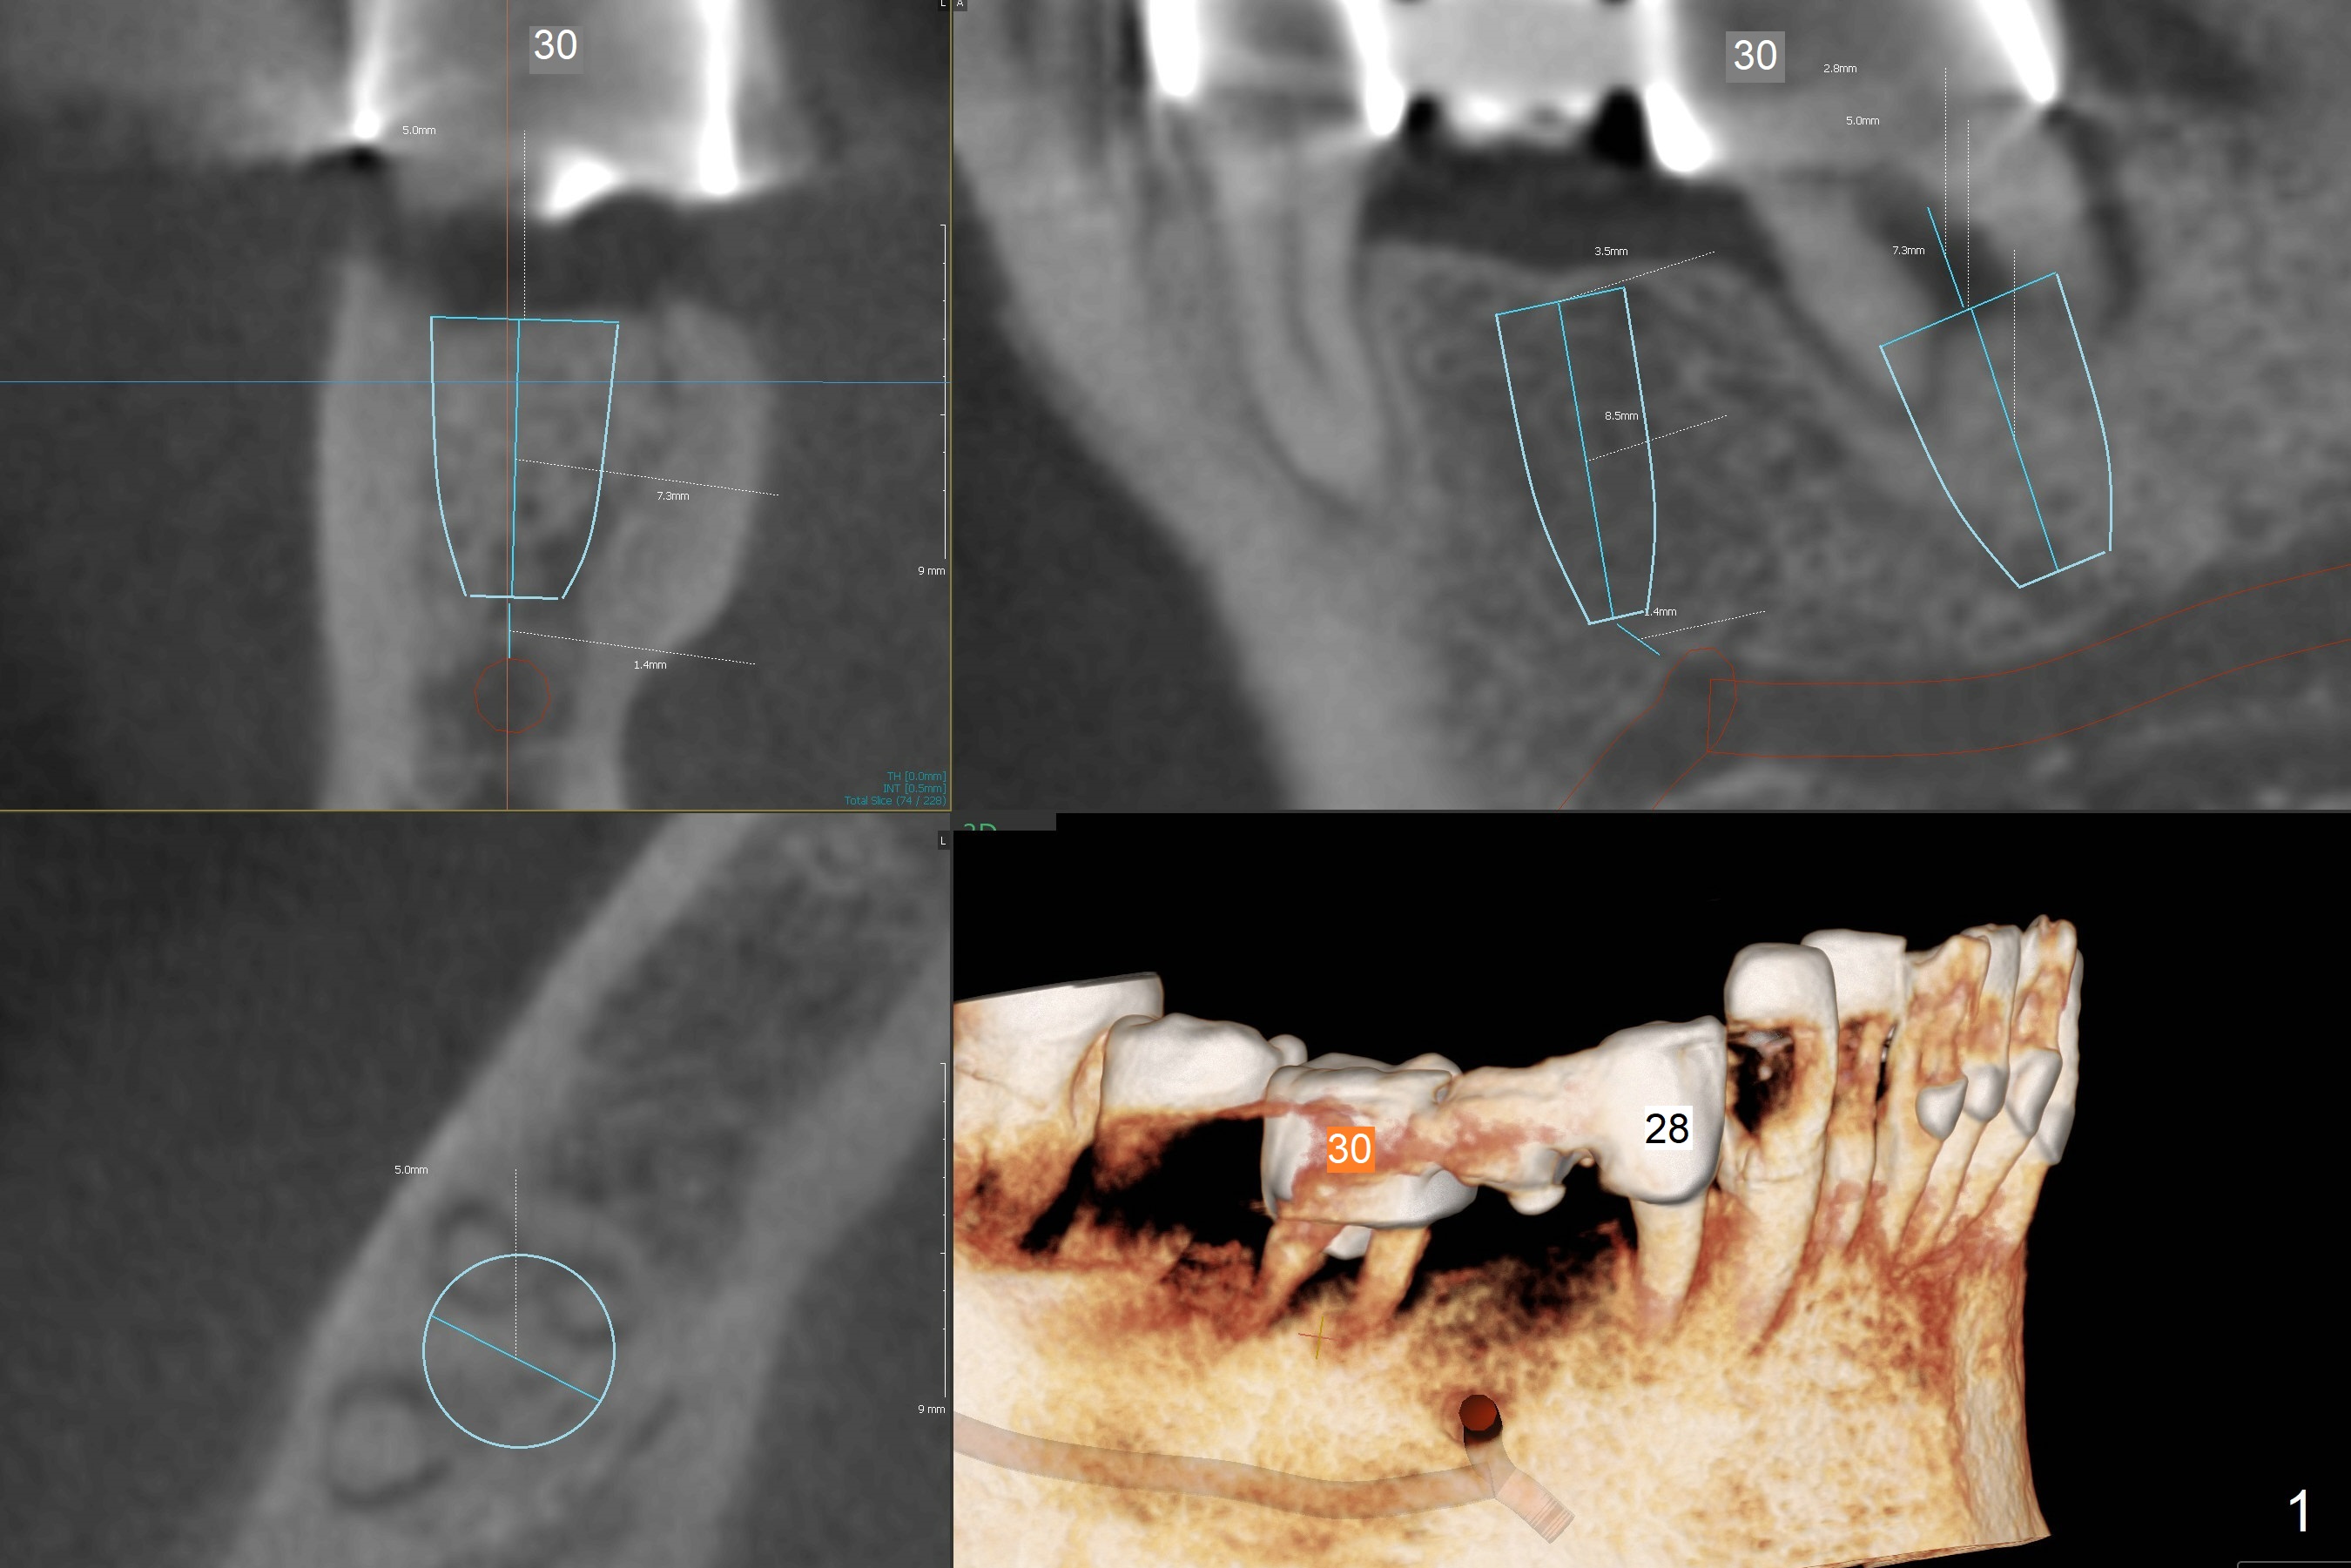

7.3 mm long Implant

A 54-year-old man has pain at #30 (Fig.1). With severe loss of bone, the tooth is non-salvageable. Section FPD between #28 and 29 before extraction of #30. Because of limited bone, 4.5x7.3 and 5x7.3 mm implants appear to be appropriate at #29 (Fig.2) and 30. Due to low bone density at #29 (Fig.2), under drilling is required.